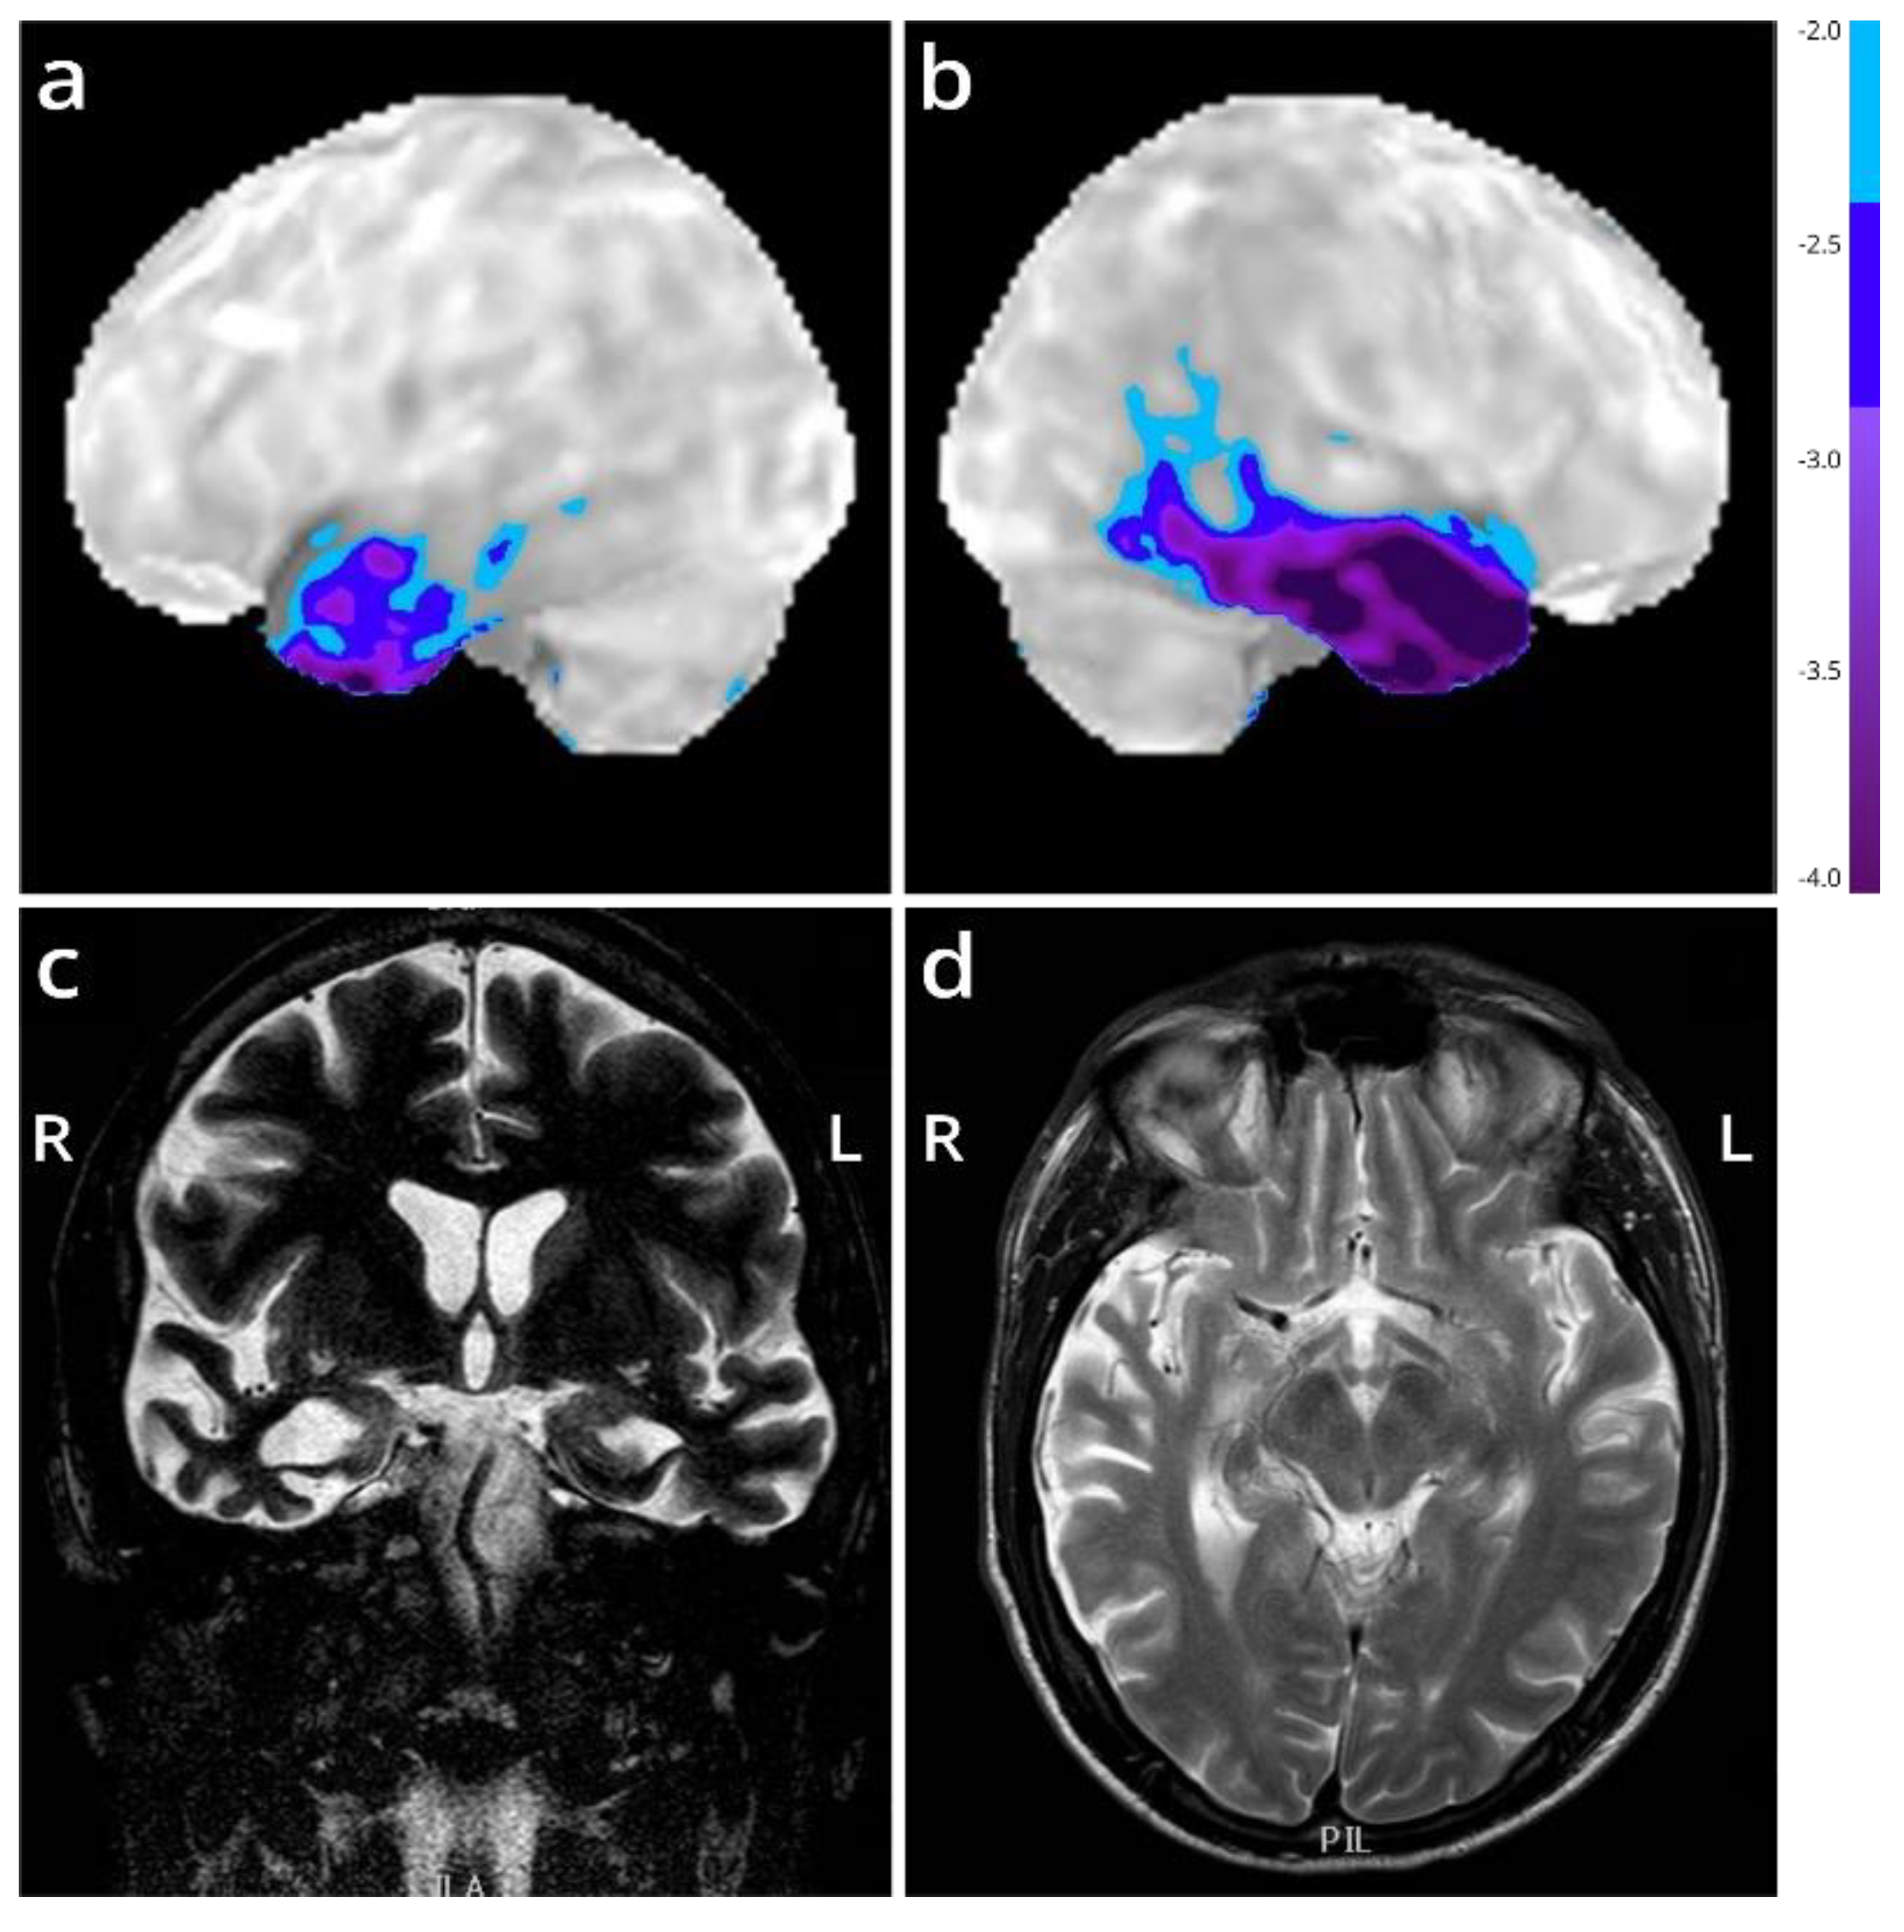

We present the autopsy case of a 60-year old man diagnosed at the age of 51 with the semantic variant of primary progressive aphasia. This was confirmed by MRI and 18F-FDG-PET, showing bilateral anterior temporal atrophy, which was more right-sided, as well as hypometabolism (Figure 1). The patient showed prosopagnosia and problems with word retrieval and word comprehension. Later on, the patient also developed behavioral changes, such as obsessive-compulsive behavior, increased appetite with loss of table manners, discrete disinhibition, loss of decorum, and emotional indifference. Additionally, the patient displayed an inexhaustible glabellar reflex and extrapyramidal symptoms such as a discrete stooped posture and a decreased arm swing. The patient did not show any signs of motor neuron disease. There was a family history of Parkinsonism on the paternal side (Figure 2). The father of the patient (Figure 2, II:1) was diagnosed with multi system atrophy (Parkinsonian type). The paternal grandmother (Figure 2, I:2) suffered from Parkinson’s disease since the age of 50. Additionally, a younger sibling of the patient was diagnosed with Parkinson’s disease (Figure 2, III:4). Exonic sequencing of the semantic dementia patient (Figure 2, III:2, red arrow) revealed a novel frameshift mutation c.187del (p.Arg64Glyfs*90) in exon 2 of the TUBA4A gene, which was absent in control individuals and public databases as previously published. Mutations in other genes causative for ALS/FTD were excluded (i.e., C9orf72, MAPT, VCP, TARDBP, FUS, SOD1, TBK1, ATXN2, UBQLN2, SQSTM1 and TREM2) [7]. Genetic testing was not performed for any of the family members of the patient.

Figure 1. Imaging of the FTD patient with an R64Gfs*90 TUBA4A mutation. (a,b) Stereotactic surface projections showing lateral views of the left (a) and right (b) hemisphere of an 18F-FDG-PET of the patient, with areas of significant decrease of glucose metabolism superimposed. The scan shows a regional decrease in glucose metabolism in the anterior temporal lobes, more pronounced to the right compared to the left. Color-coding refers to Z-scores with respect to a dataset of normal control subjects. (c,d) MRI (T2-weighted) at the level of the temporal lobe (coronal in (c); horizontal in (d)) shows temporal lobar degeneration typical for FTLD. L = left; R = right.